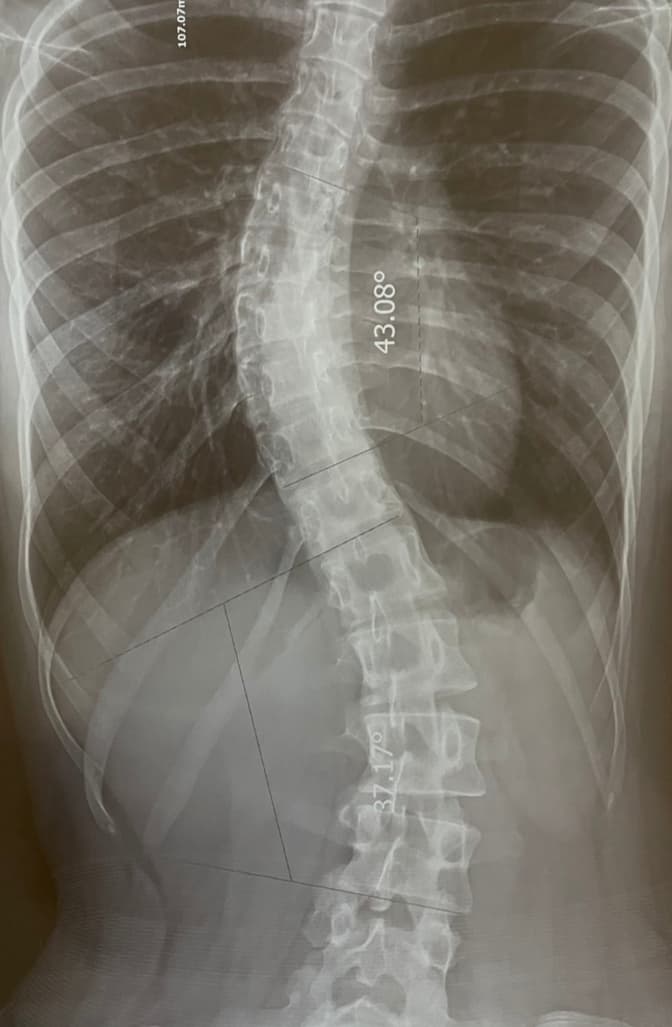

У Львівській обласній дитячій клінічній лікарні ОХМАТДИТ прооперували 16-річну Вікторію із ідіопатичним сколіозом IV-м ступеня.

Як йдеться у повідомленні Львівської обласної дитячої клінічної лікарні ОХМАТДИТ, у дівчини важкий юнацький сколіоз не відомого походження виявили більше трьох років тому. Певний час їй призначили консервативну терапію – вона носила спеціальний корсет, але це не допомогло. Тоді батьки Вікторії, пропри ризики ускладнення, погодилися на оперативне втручання. Але війна в Україні поставили рішення батьків на паузу, що негативно впливало на стан здоров’я дитини.

Майже чотиригодинне оперативне втручання з корекції деформації хребта хірургічним шляхом із застосуванням конструкції пройшла успішно і без ускладнень. На другий день дівчина вже стояла на ногах. Упродовж тижня вона ще проходитиме реабілітацію у лікарні, а до місяця часу відновлюватиметься вдома.